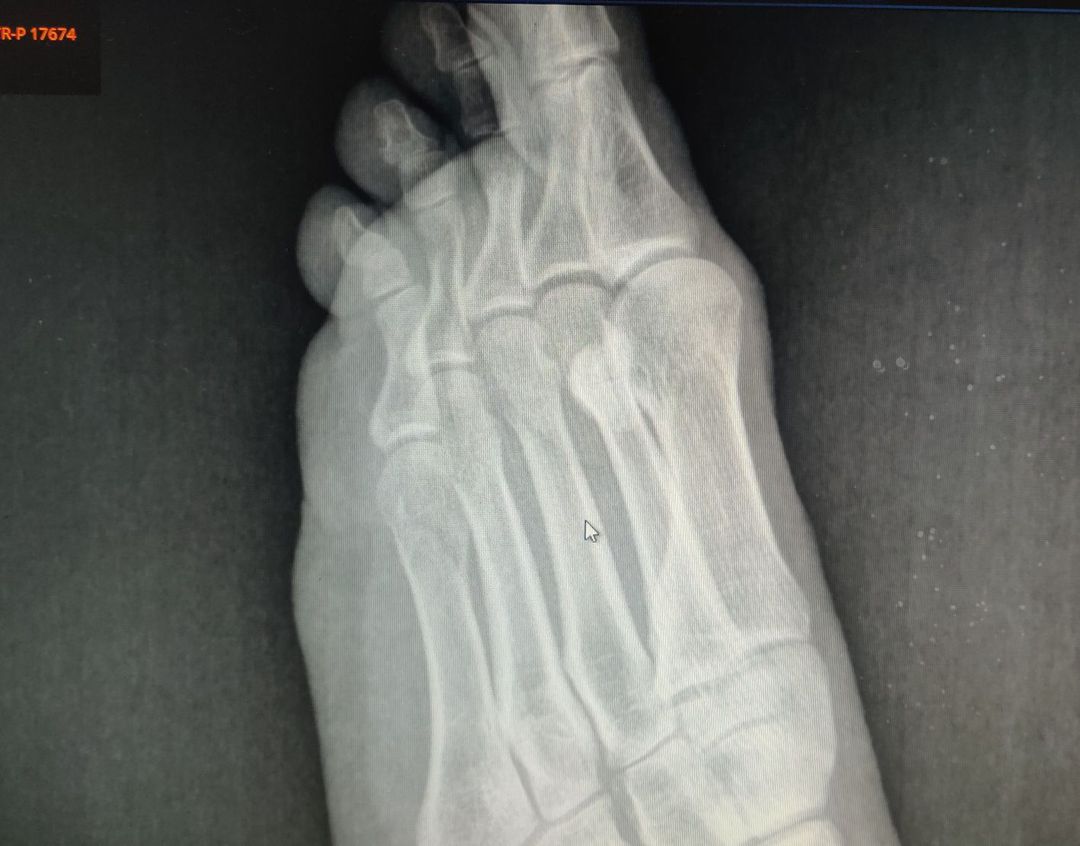

Fracture of the head of 5 metatarsal bone

Xray

Fracture

Traumatology